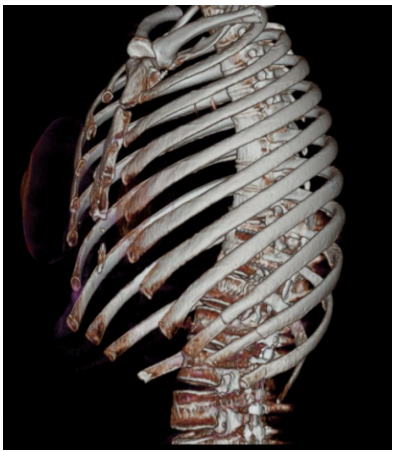

Mulher, 46 anos de idade, apresentou trauma torácico em

acidente com queda da motocicleta. Foi realizada a

tomografia computadorizada de tórax, conforme imagem a

seguir:

Em relação ao caso descrito, assinale a alternativa que apresenta os sinais/sintomas clínicos típicos dos achados da tomografia apresentada.

Em relação ao caso descrito, assinale a alternativa que apresenta os sinais/sintomas clínicos típicos dos achados da tomografia apresentada.